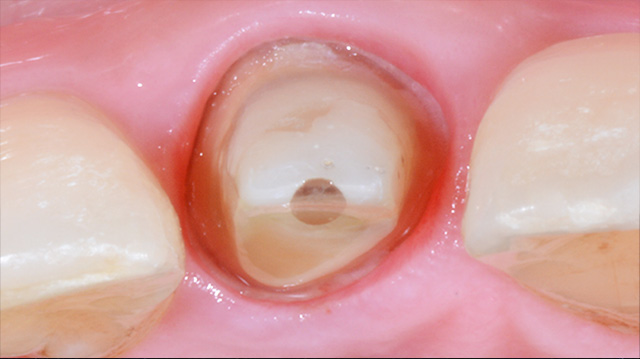

| 年代・性別 | 50代 男性 |

|---|---|

| 主訴 | 転倒して歯が割れた |

| 治療回数 | 3回 |

| 治療期間 | 約1ヶ月 |

| 費用 | 仮歯 5,500円 ジルコニアクラウン 176,000円 |